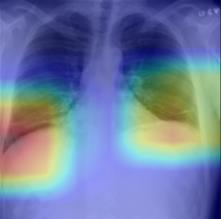

Thoracic disease detection from chest radiographs using deep learning methods has been an active area of research in the last decade. Most previous methods attempt to focus on the diseased organs of the image by identifying spatial regions responsible for significant contributions to the model's prediction. In contrast, expert radiologists first locate the prominent anatomical structures before determining if those regions are anomalous. Therefore, integrating anatomical knowledge within deep learning models could bring substantial improvement in automatic disease classification. This work proposes an anatomy-aware attention-based architecture named Anatomy X-Net, that prioritizes the spatial features guided by the pre-identified anatomy regions. We leverage a semi-supervised learning method using the JSRT dataset containing organ-level annotation to obtain the anatomical segmentation masks (for lungs and heart) for the NIH and CheXpert datasets. The proposed Anatomy X-Net uses the pre-trained DenseNet-121 as the backbone network with two corresponding structured modules, the Anatomy Aware Attention (AAA) and Probabilistic Weighted Average Pooling (PWAP), in a cohesive framework for anatomical attention learning. Our proposed method sets new state-of-the-art performance on the official NIH test set with an AUC score of 0.8439, proving the efficacy of utilizing the anatomy segmentation knowledge to improve the thoracic disease classification. Furthermore, the Anatomy X-Net yields an averaged AUC of 0.9020 on the Stanford CheXpert dataset, improving on existing methods that demonstrate the generalizability of the proposed framework.